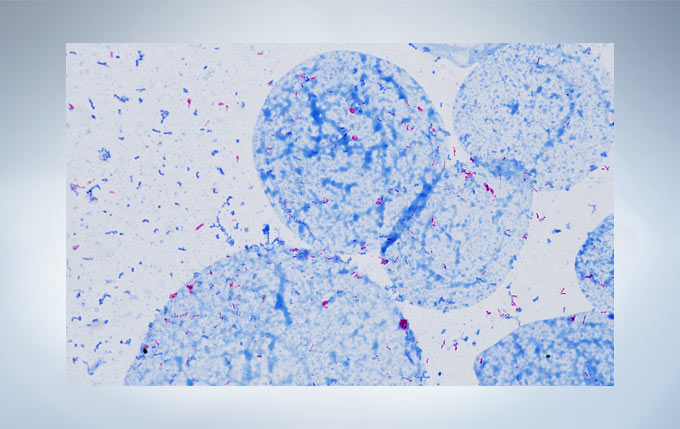

显微镜采用平场消色差物镜,让大视野观察图像清晰且平整度更好。这使用户在常规显微观察时,样品既清晰又均匀平坦。